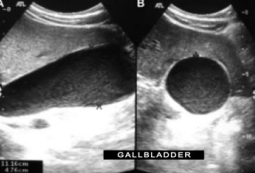

Describe this image

Dx:

Gallbladder in both the longitudinal and transverse planes with low level echoes suggestive of sludge and distention (gallbladder hydrops).

Dx: Likely diagnosis is choledocholithiasis